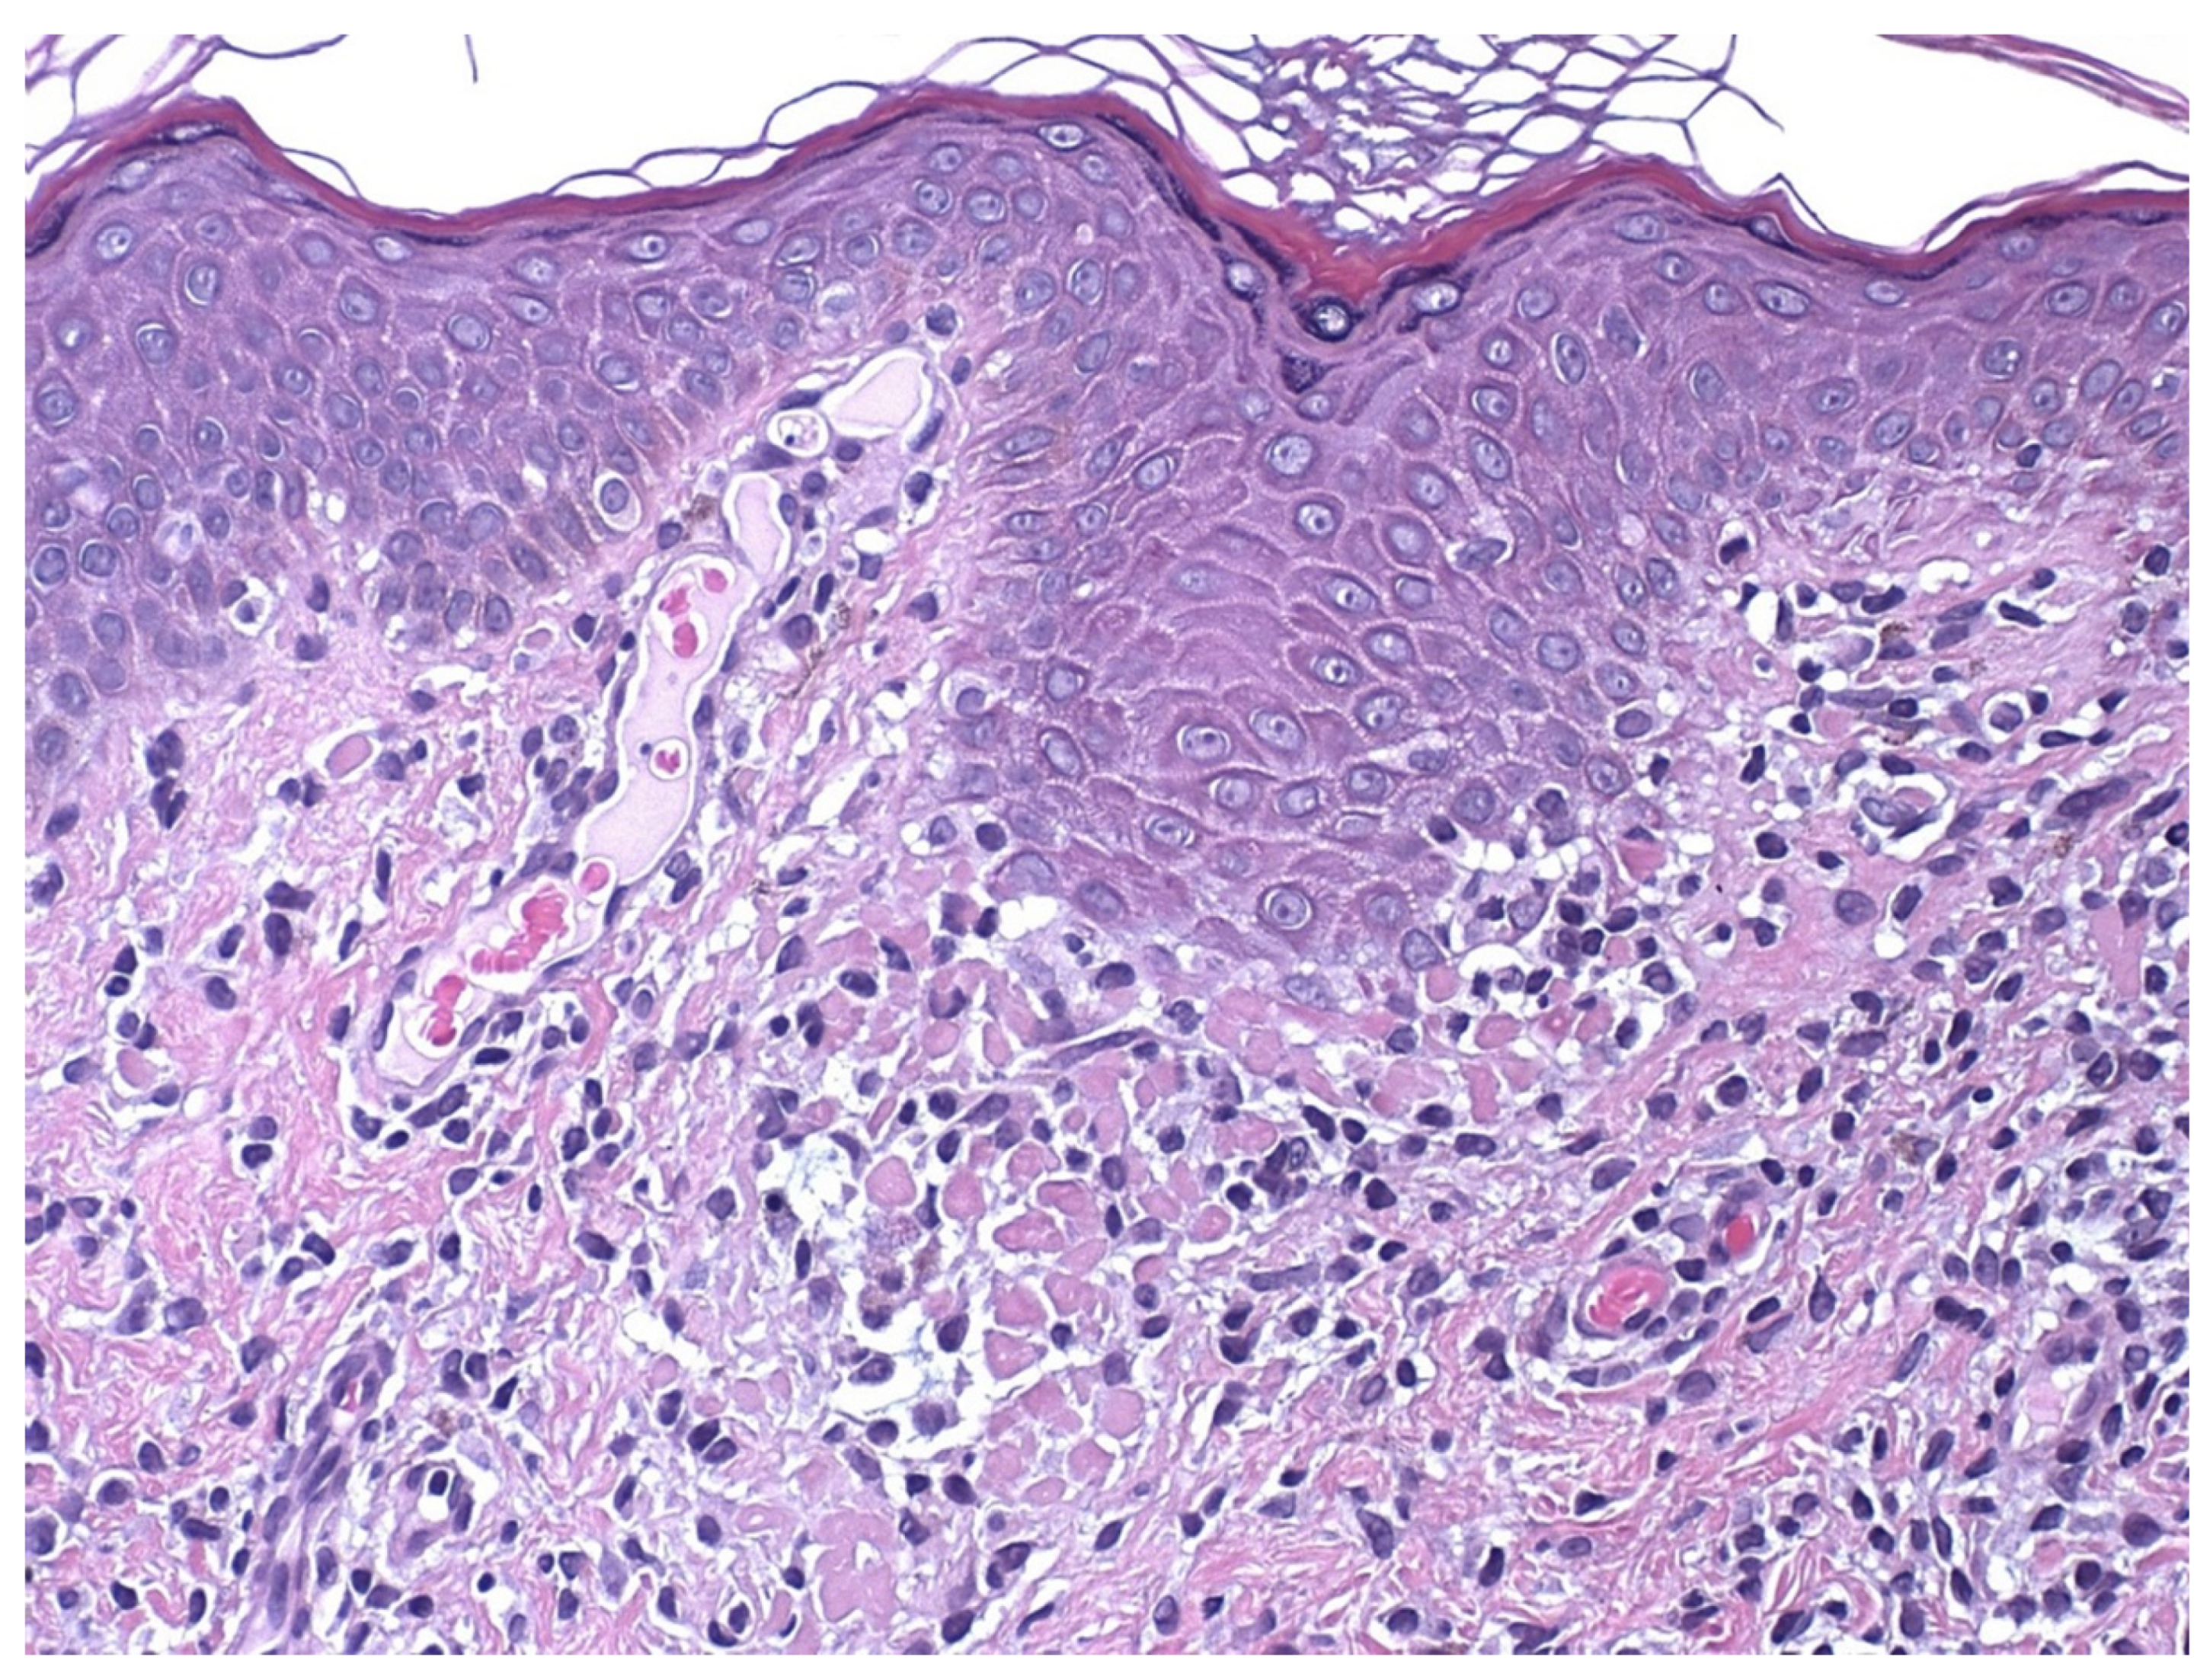

4. Histopathology